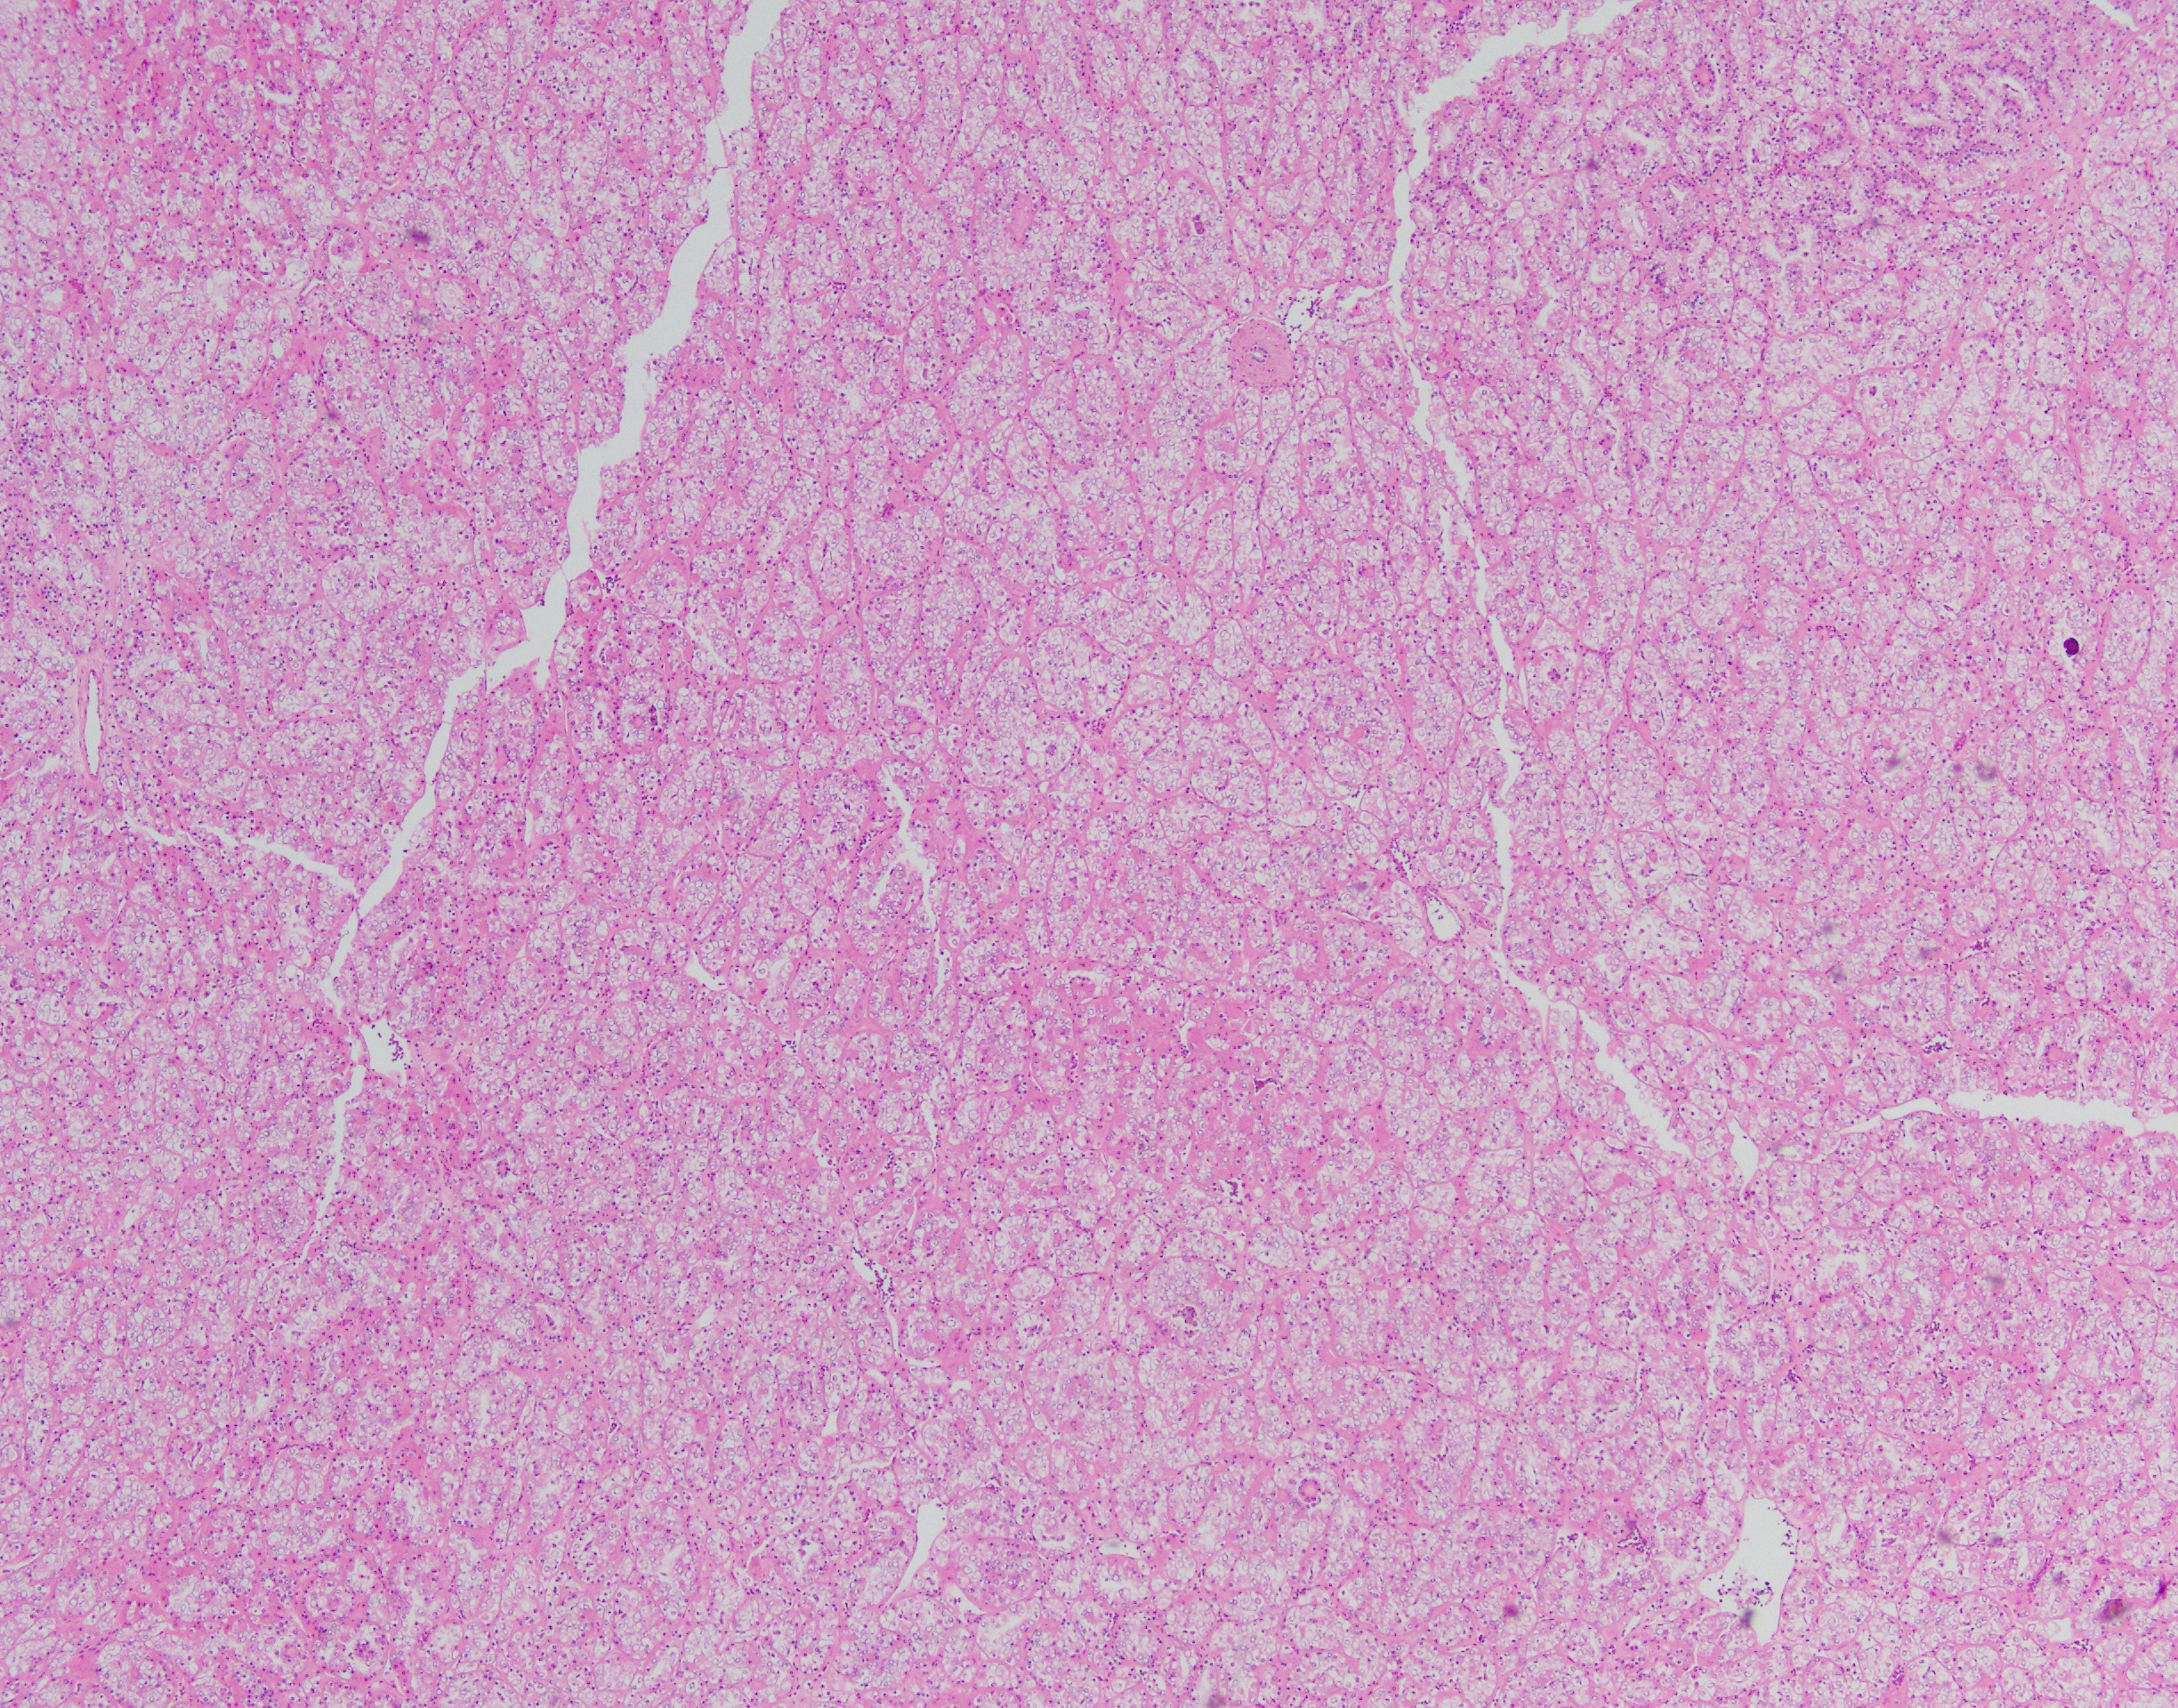

The neoplasm has a compact architectural growth pattern with confluent anastomosing cords, tubules and acini. The tumor cells have granular eosinophilic cytoplasm containing glycogen. The nuclei are round to oval with slightly irregular contours, having a distinct chromatin pattern with condensation at the periphery with clearing of the central portion.

Translocation-associated RCCs involve the MiTF/TFE (Microphthalmia-associated transcription factor/transcription factor binding to IGHM enhancer 3) family genes. The primary genes involved are either TFE3 (located at Xp11.2) or TFEB (located at 6p21.1). Due to the relatively small number of cases studied so far, knowledge of the clinical aspects and outcome of these tumors is not complete. They do represent at least 20% of RCCs in the pediatric age group. Histologically, t(6;11) carcinomas usually consist of nests and microscopic cysts composed of polygonal cells with pale or eosinophilic cytoplasm. Papillae are uncommon. These cells can be arranged around nodules of hyaline material in large acini.